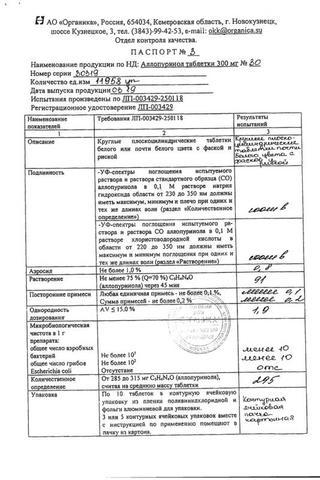

Аллопуринол таблетки 300 мг 30 шт

Аллопуринол: Состав

Таблетки белого или белого с желтоватым оттенком цвета, круглые, плоскоцилиндрические, с риской и фаской.

1 таб.

аллопуринол 100 мг

Вспомогательные вещества: целлюлоза микрокристаллическая (МКЦ-101 Премиум) - 54 мг, крахмал кукурузный - 25 мг, карбоксиметилкрахмал натрия - 10 мг, повидон К25 - 8 мг, кремния диоксид коллоидный - 1 мг, магния стеарат - 2 мг.

10 шт. - упаковки ячейковые контурные (1, 2, 3, 4, 5, 6, 7, 8, 9 или 10 шт.) - пачки картонные.

14 шт. - упаковки ячейковые контурные (1, 2, 3, 4, 5, 6, 7, 8, 9 или 10 шт.) - пачки картонные.

25 шт. - упаковки ячейковые контурные (1, 2, 3, 4, 5, 6, 7, 8, 9 или 10 шт.) - пачки картонные.

30 шт. - упаковки ячейковые контурные (1, 2, 3, 4, 5, 6, 7, 8, 9 или 10 шт.) - пачки картонные.